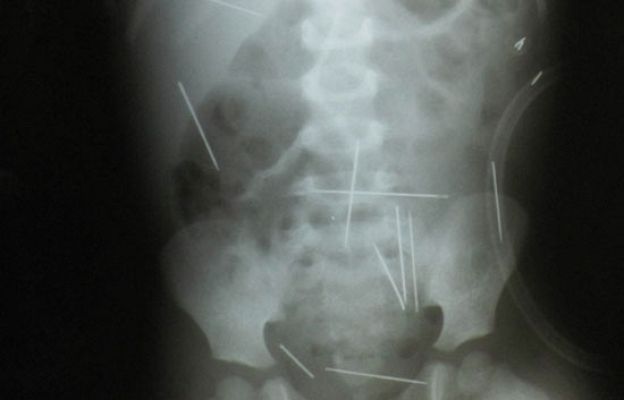

Un niño de dos años tiene cerca de cincuenta agujas dentro del cuerpo | Ver

Niño tiene 50 agujas en su cuerpo

El médico que lo trata ha dicho que intentará sacárselas pero que es difícil porque algunas están demasiado cerca de órganos vitales.(16/12/09)